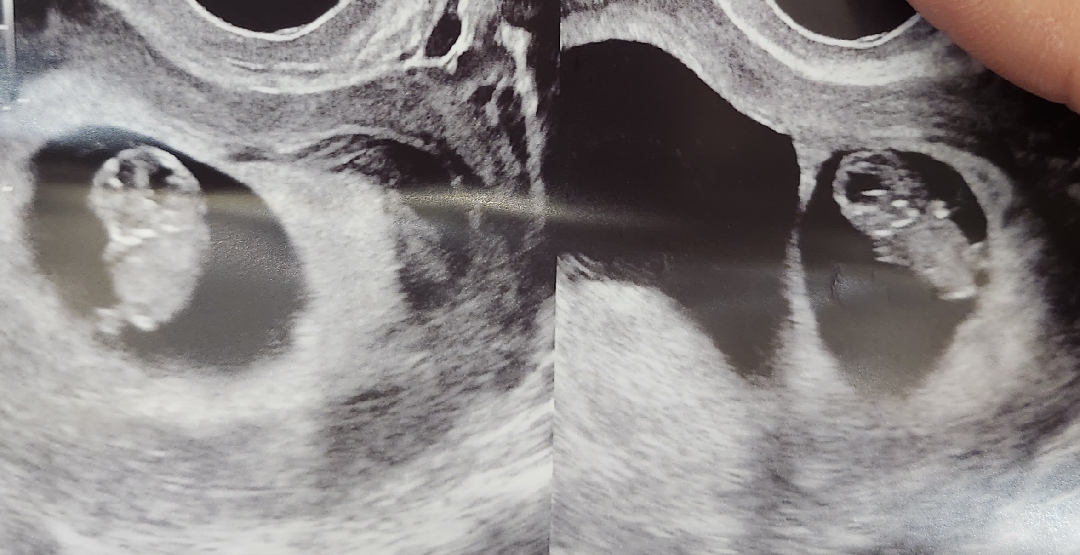

쌍둥이 젤리곰 보고 왔어요!

8주 6일차 쌍둥이맘이에요. 첫째는 옆으로 웅크리고 둘째는 앞으로 보고 있는데 초음파 보는 순간 막 파닥파닥 거리더라구요! 넘 귀여운거 있죠 ㅋㅋㅋ 무럭무럭 잘 자라고 있대요. 너무 귀여워요 벌써 도치맘 예약 🙄